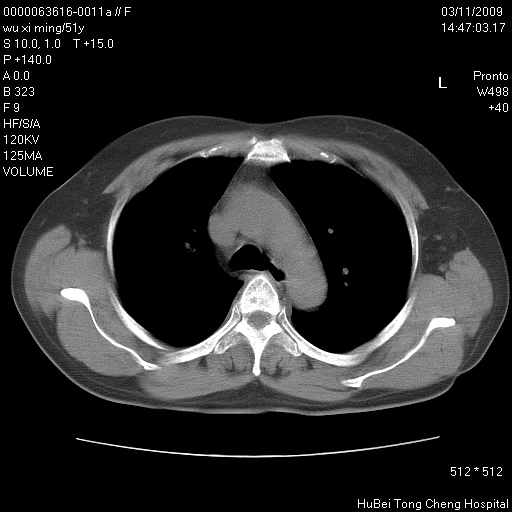

患者 女,51岁。因“胆囊炎,胆囊结石”,行常规术前胸部x线检查发现:右上肺结节病灶,建议行进一步检查。患者无咳嗽、咳痰及咯血等呼吸道症状,近期出现背部疼痛不适。

胸部ct轴位平扫(层厚10mm,螺距1.5,重建间隔10mm;部分层面:层厚3mm,螺距1.0,重建间隔3mm),图像如下:

1、周围型肺癌。(毛刺正、血管束集征,分叶。)

集束征,胸膜牽拉征,毛刺,淺分葉高度提示ca.

右肺周围型肺癌伴肺内转移及胸椎转移。已无手术机会。